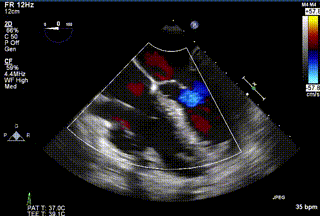

三例患者入院后,葛均波院士團隊周達新教授、潘文志教授、張源博士、陳莎莎博士及心超室的潘翠珍教授、李偉教授對患者的情況進行詳細評估和討論,最終決定為三例患者選擇LuX-Valve Plus40mm、50mm和50mm型號的瓣膜進行手術治療。手術后即刻拔除氣管插管,術后患者三尖瓣反流癥狀得到顯著改善,復查心超結果顯示人工三尖瓣瓣膜支架固定穩(wěn)定,瓣葉關閉形態(tài)未見異常,未見明顯反流。